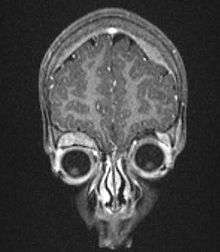

On microscopy, the tumor cells are typically described as small, round and blue, and rosette patterns (Homer Wright rosettes) may be seen. Homer Wright rosettes are tumor cells around the neuropil, not to be confused with pseudorosettes, which are tumor cells around a blood vessel.[25] They are also distinct from the pseudorosettes of an ependymoma which consist of tumor cells with glial fibrillary acidic protein (GFAP)–positive processes tapering off toward a blood vessel (thus a combination of the two).[26] A variety of immunohistochemical stains are used by pathologists to distinguish neuroblastomas from histological mimics, such as rhabdomyosarcoma, Ewing's sarcoma, lymphoma and Wilms' tumor.[27]